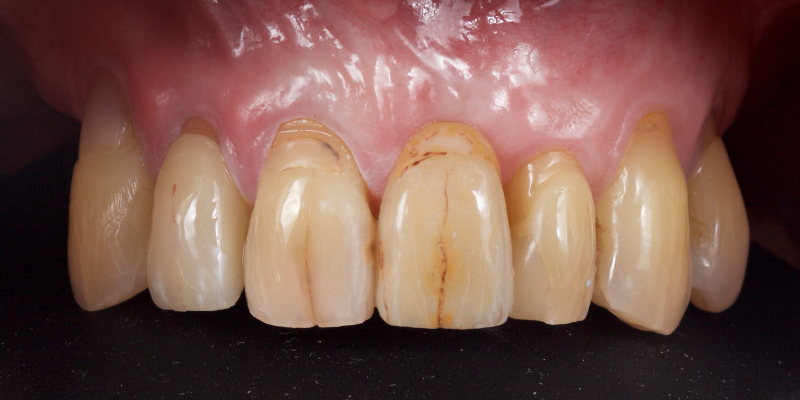

Take Arthur, a 76-year-old man who presented with a vertical root fracture of his upper left central incisor. His medical conditions precluded his request for an implant, so he agreed to the proposal for an adhesive bridge instead.

The tooth was extracted and for four months the pontic site was conditioned with a removable Essix-type of denture (Fig. 1).

An e.max (lithium disilicate), one-wing (adjacent central being the retainer) bridge was placed, which resulted in an acceptable outcome (Figs. 2-4) that was more timely and at a lower financial and biological cost to the patient than the implant Arthur initially thought he wanted.